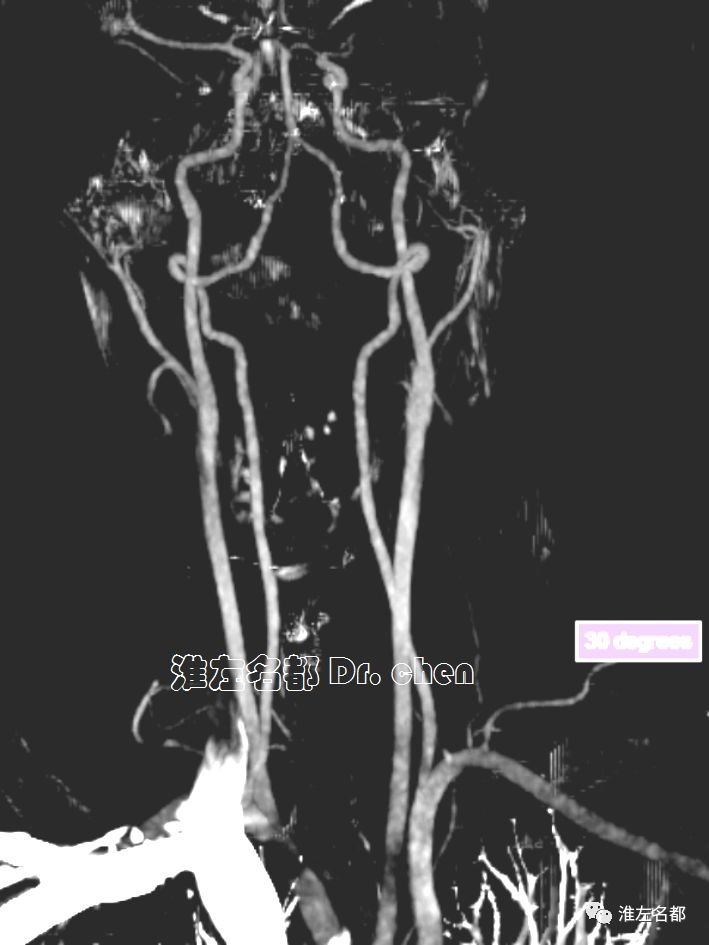

△头颅CTA:左侧颈内动脉末端和大脑中动脉未见显影;左侧颈内动脉显影较右侧细小,造影剂浓度淡(提示血流缓慢)。

△颈部CTA:颈部动脉未见异常。